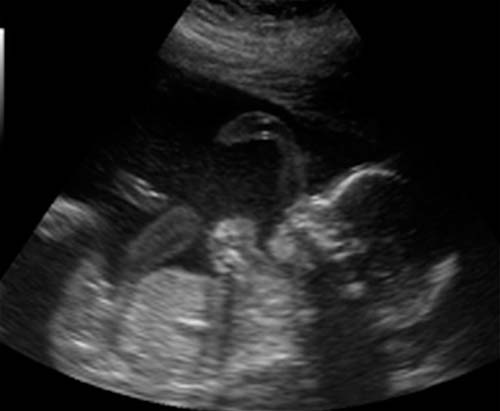

Si vous n'avez pas subi d'échographie au cours du deuxième trimestre, il sera nommé. Un médecin spécialiste vérifiera les principales dimensions du corps et des membres du fœtus, l'état des organes internes et un certain nombre d'autres indicateurs. Le placenta ne sera pas moins examiné en profondeur.

Photo échographique à 21 semaines (cliquez pour agrandir):

Avec un emplacement réussi du fœtus, vous pouvez découvrir le sexe du bébé. Mais le futur garçon ou fille peut parfois «se cacher» jusqu'à la naissance même.